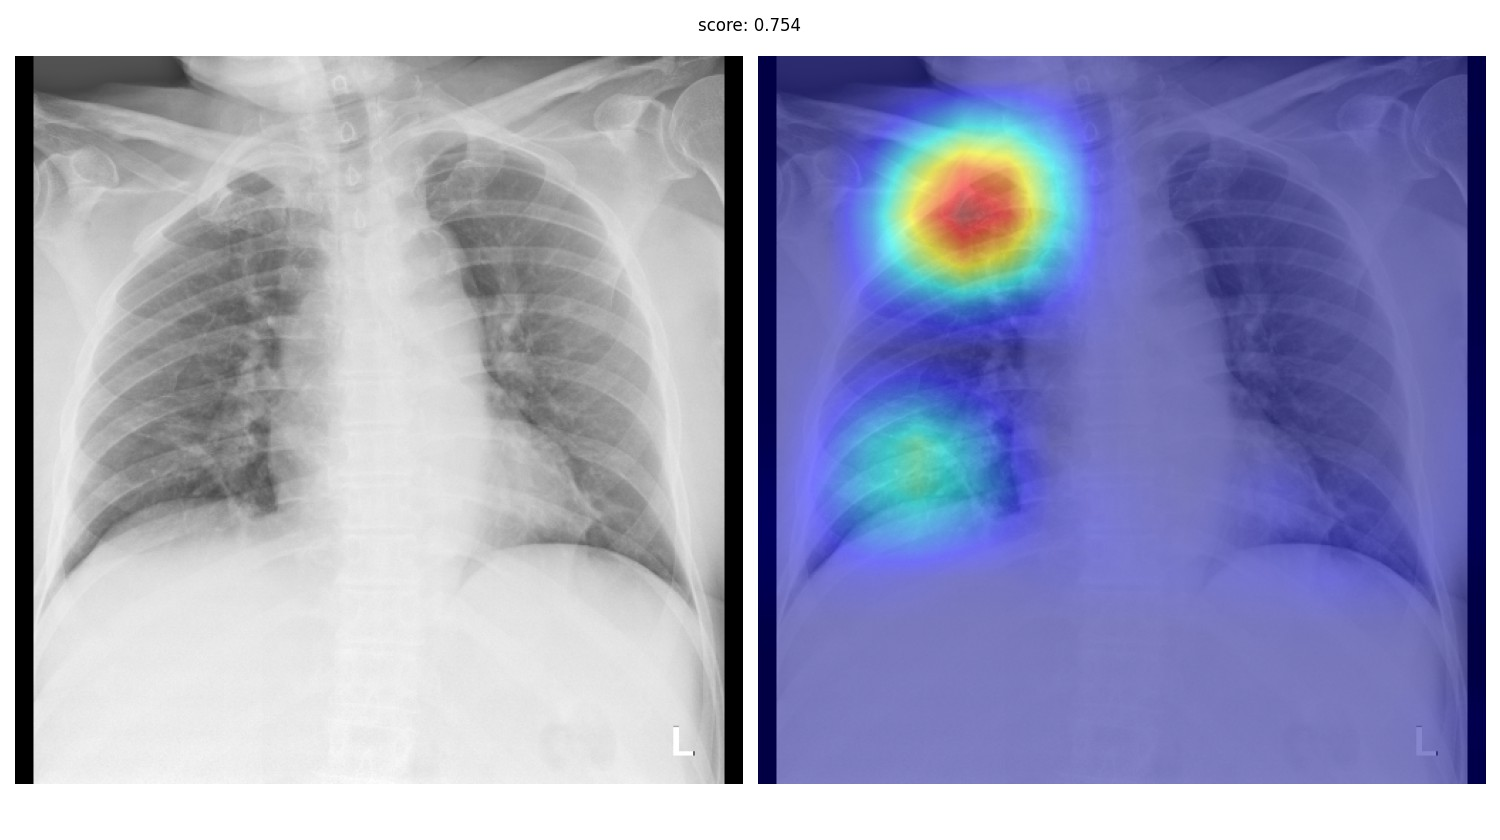

Что такое интерпретируемость, если решается задача классификации всего рентгенологического исследования - в целом понятно. Врачи не доверяют системам, которые просто говорят “тут где-то на картинке есть рак”, а значит нужны какие-то методы, которые будут “объяснять” итоговое предсказание. Их придумано довольно много - разнообразные виды GradCAMа, окклюзия, LIME. Из коробки многие из них можно взять из библиотеки Captum для Pytorch.

Несколько месяцев в 2020 году GradCAM работал у нас в продакшне

Однако, жизнь показывает, что качество локализации клинически значимых признаков у этих методов, мягко говоря, неудовлетворительное. При этом вряд ли кто-то будет всерьёз рассматривать ИИ-систему, которая не решает задачу локализации - детекции или сегментации. Да и реально хороших метрик на чистой классификации достичь удаётся разве что при наличии очень больших, чистых датасетов. На данный момент у нас четыре системы в проде, из них одна - это детекция, две - инстанс-сегментация, и ещё одна - семантическая сегментация.